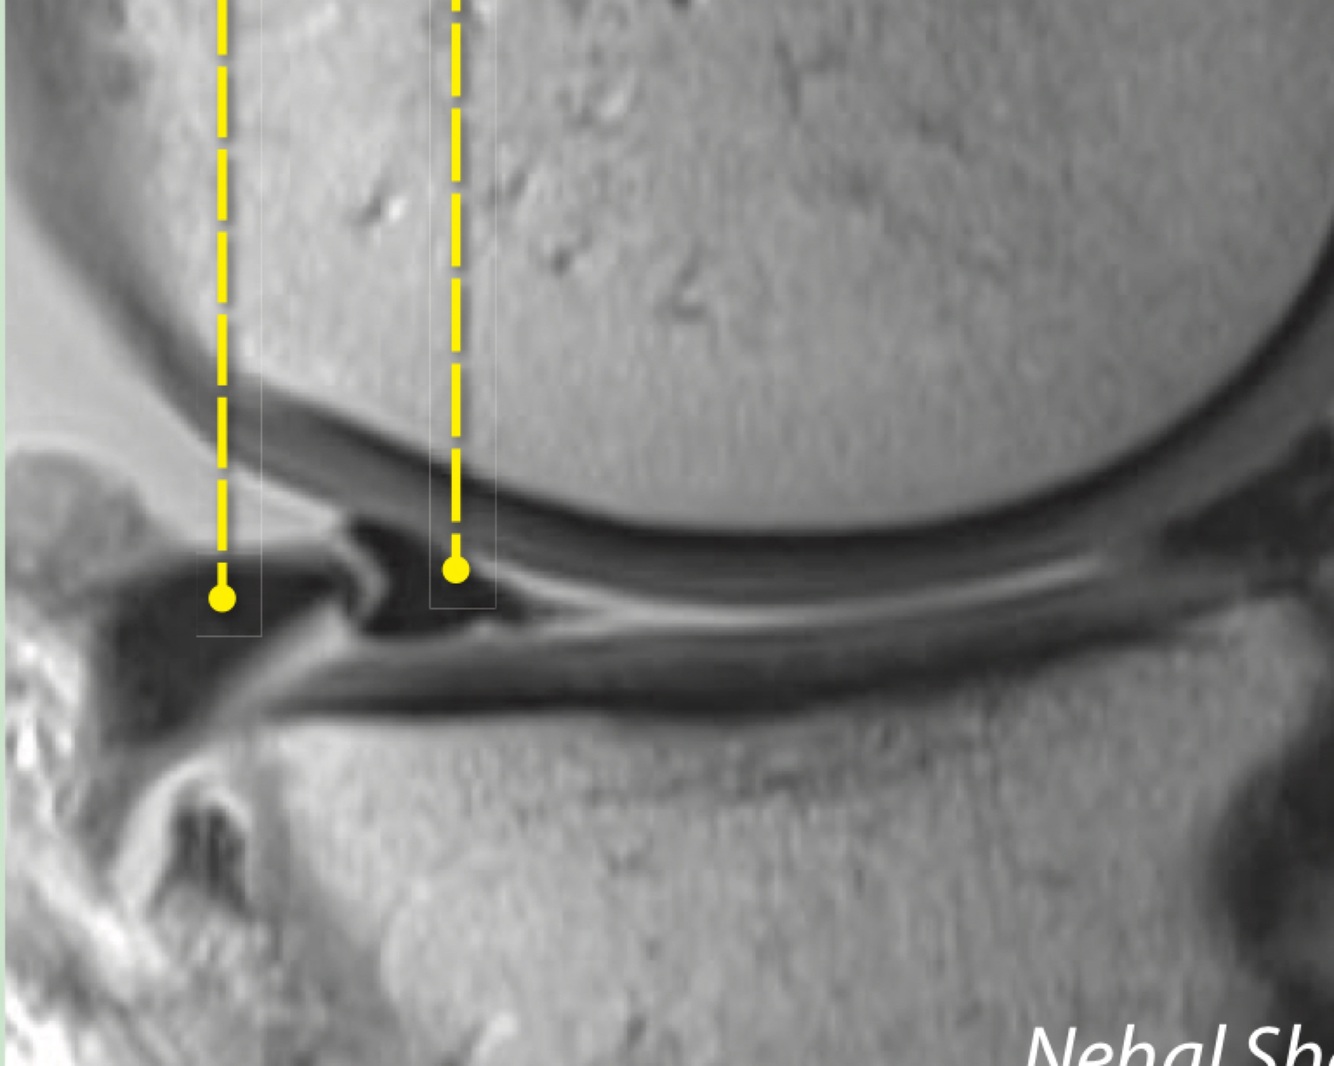

19

Q

What sign is this and what does it indicate

A

Double delta sign - anteriorly flipped displaced bucket handle fragment of lateral meniscus tear

How well did you know this?